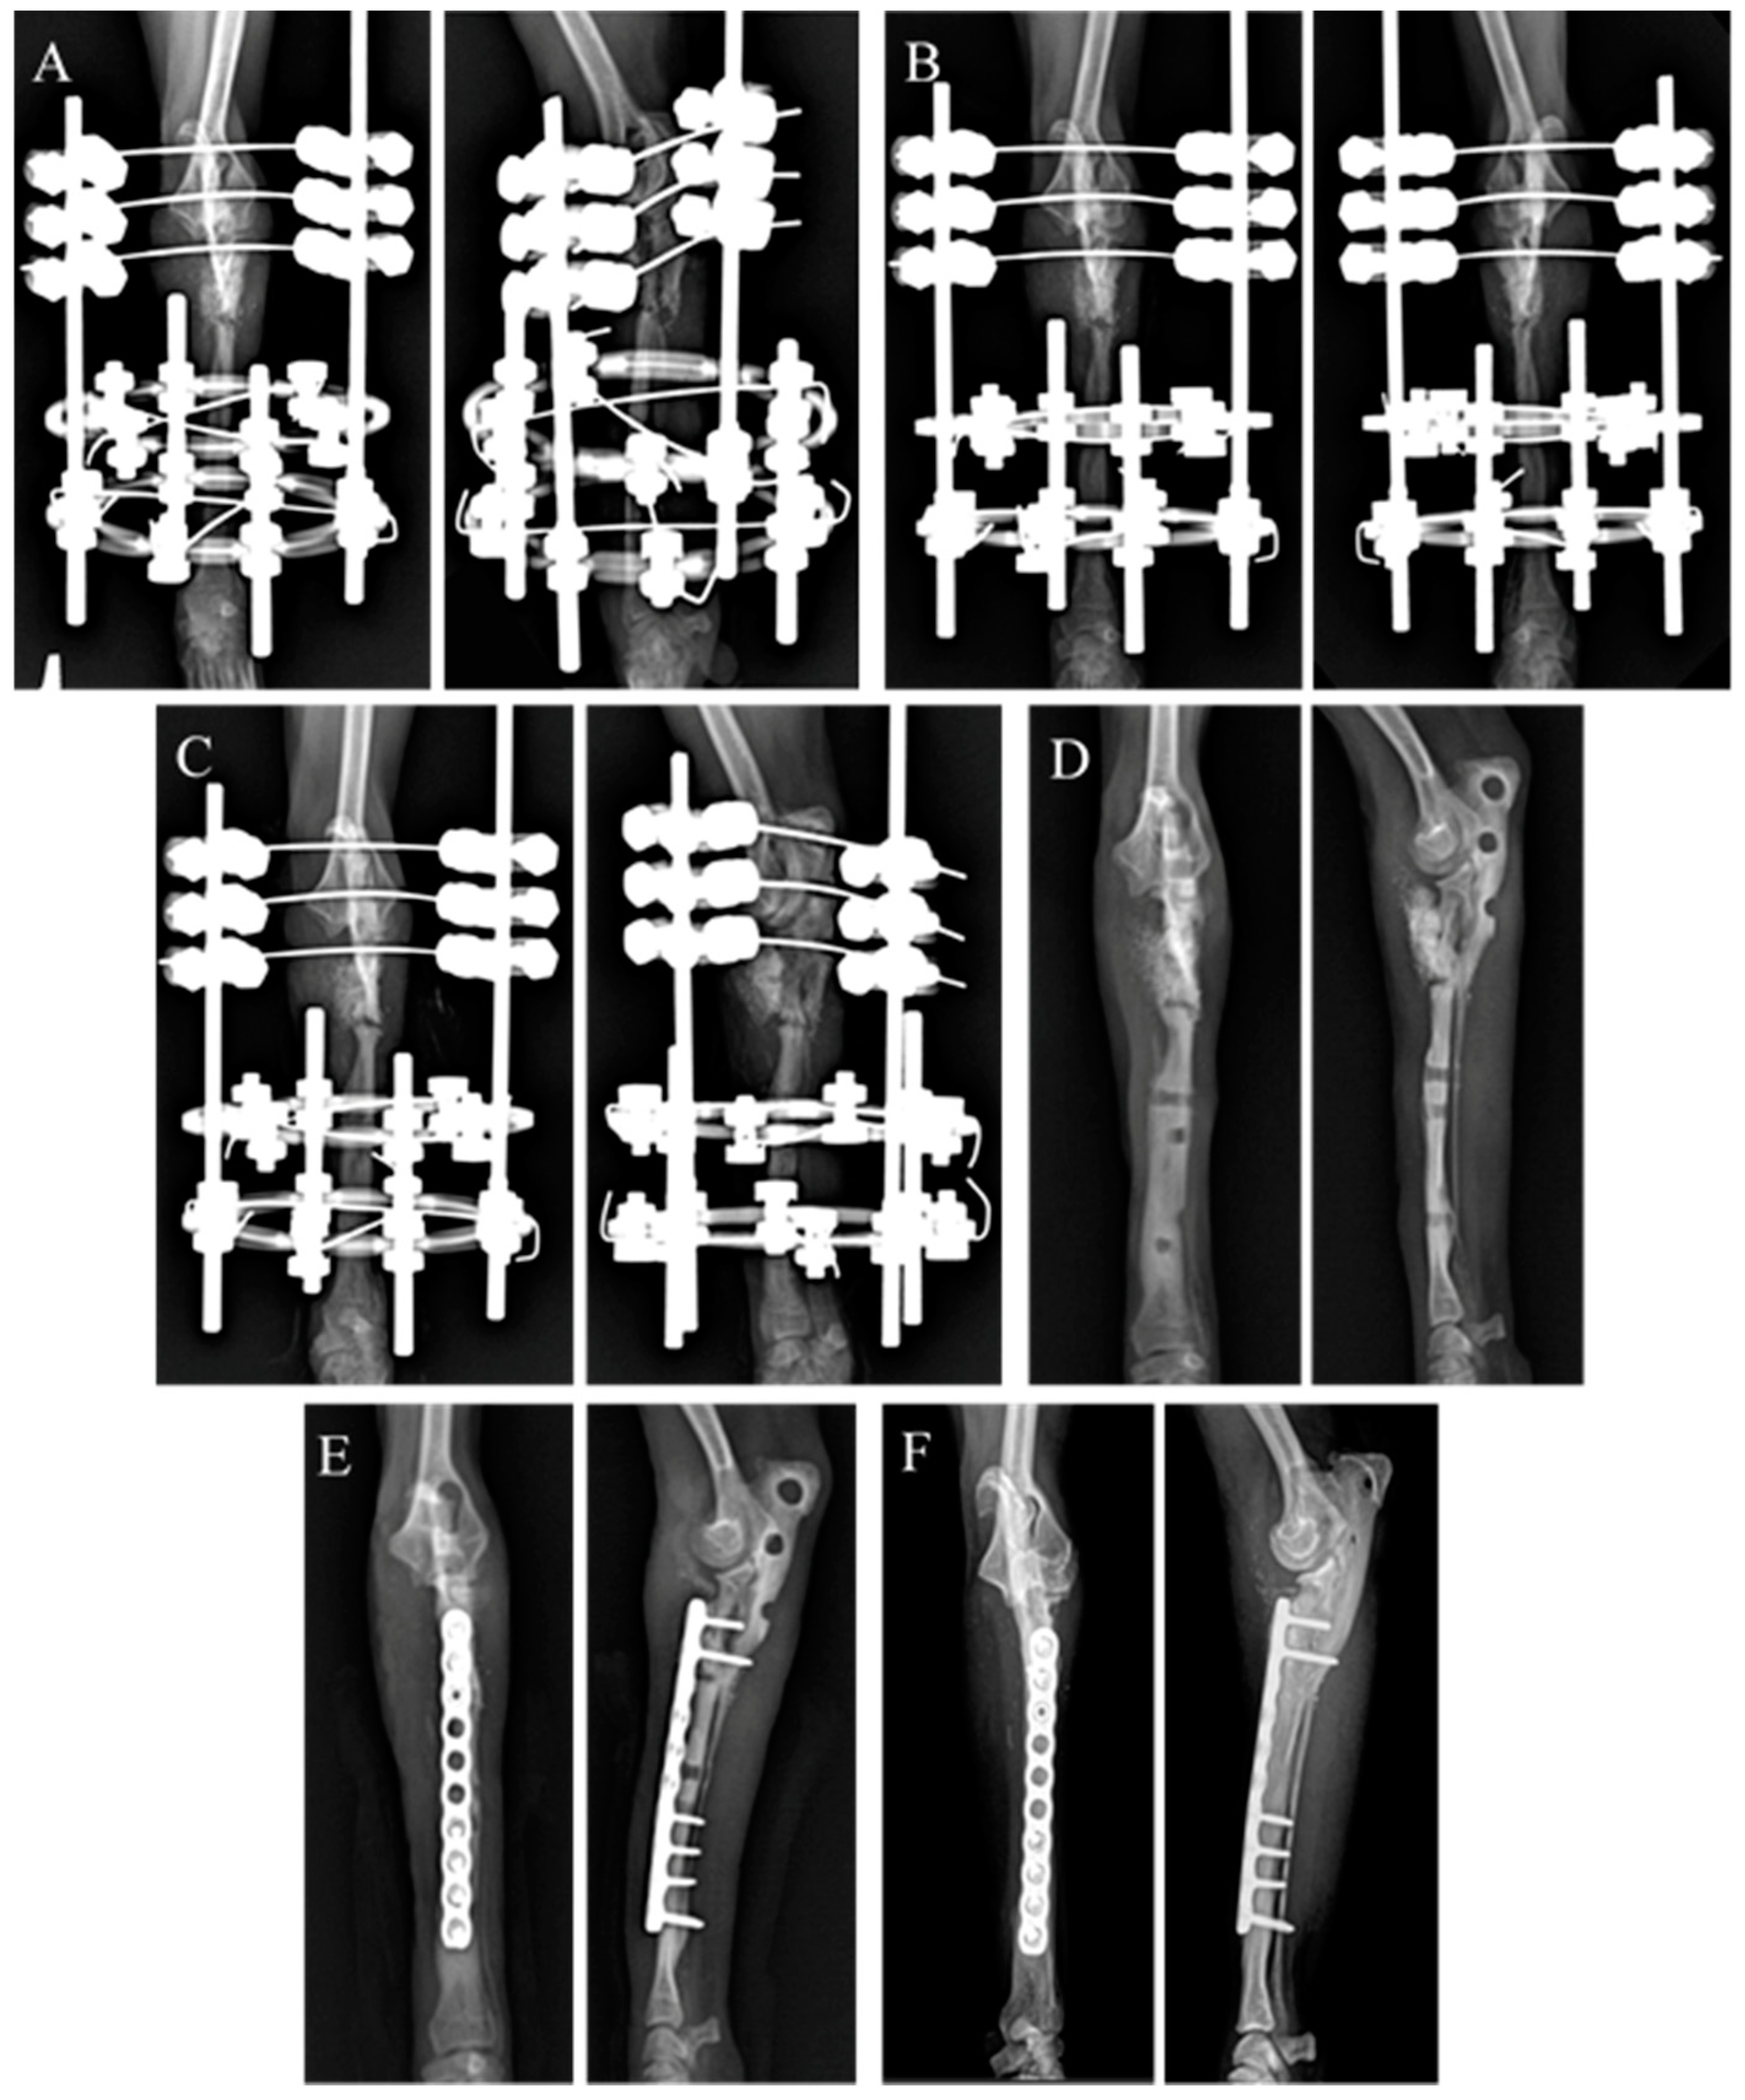

One month after the first surgery, radiography revealed bone regeneration at the radial head. Two months following surgery, bone continuity and sufficient size (18.8 mm × 7.5 mm) of the proximal radial head fragment for screw placement were observed. However, loosening of the proximal pins and widening of the ESF pinholes were also noted, leading to the decision that revision surgery was necessary.

One month after the first surgery, radiographic evaluation revealed bone regeneration of the radial head, with maintenance of the ESF and connection of the proximal three fragments. Two months after surgery, the upper radial head formed a single segment (18.8 mm × 7.5 mm), allowing sufficient space for plate fixation, even without hybrid ESF. Therefore, a revision surgery was performed using plate fixation to correct the radius defects and provide a more stable biomechanical environment for the healing bone.

Two weeks after the second surgery, the ROM of the affected limb’s elbow joint was found to be mildly reduced by 10–20% compared to that of the normal limb. Radiography revealed that the radial head was positioned below the typical location, resulting in decreased joint congruity. However, the overall condition of the joint improved compared to that at the initial visit, and continuity of the bone within the defect areas was observed. Five weeks after the second surgery, partial recovery of the asymmetrical gait was revealed. Nine weeks after the second surgery, the patient’s gait had improved, and the clinical lameness score criteria revealed 8 points out of 27 points.

At the 4.8 years long-term follow-up visit, the owner reported no forelimb-related clinical signs such as lameness. Radiographically, evidence of synostosis between the proximal ulna and radius along with mild osteoarthritis were observed in the affected elbow joint (Figure 5). Furthermore, on CT, while the lengths of both humeri were nearly the same, the right radius was 83.5 mm and the left radius was 70 mm, meaning that the length of the affected limb was approximately 17% shorter than that of the normal limb.

Figure 5. Sequential radiographic images are shown at 0 days (A), 4 weeks (B), and 8 weeks (C) after fixation of the hybrid ESF with bone graft materials. (D) Due to ESF pin hole defects, plate fixation with bone graft materials was performed at 12 weeks (E). Radiography showing radioulnar synostosis (F) 4.8 years after the insertion of the plate.